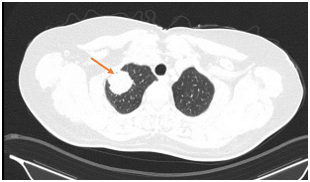

Hình 1. Nhu mô gan phải có nốt ngấm thuốc kém chủ yếu ngấm viền ngoại vi đường kính ~ 25mm